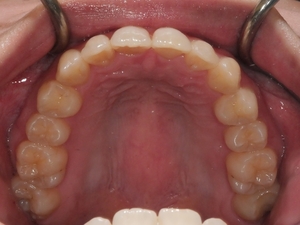

ガタガタとした歯並びや八重歯(叢生)CASE63